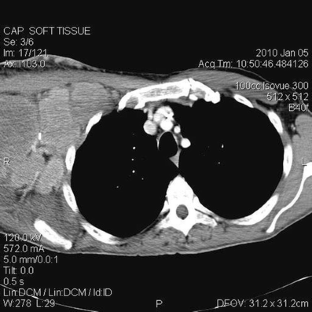

Sikaria, S., Heim-Hall, J., Diaz, E.H. et al. Partial response of a rare malignant metastatic diffuse tenosynovial giant cell tumor with benign histologic features, treated with SCH 717–454, an insulin growth factor receptor inhibitor, in combination with everolimus, an MTOR inhibitor. Targ Oncol 9, 73–79 (2014). https://doi.org/10.1007/s11523-013-0267-8